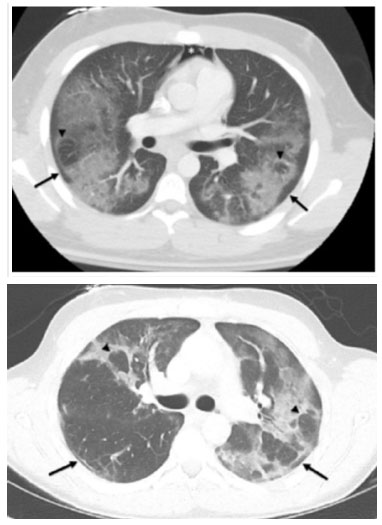

In general, EVALI presents nonspecific findings on imaging tests. The most frequently reported findings are bilateral ground-glass opacities with areas of consolidation, often with a peculiar pattern of subpleural sparing and the presence of a reverse halo sign[25] (Figure 1).

In a multicentric cohort, Kligerman et al. [28] analyzed chest tomography (CT) scans of 160 patients with EVALI. In this study, most patients had a predominantly ground-glass symmetric lung lesion, with the level of consolidation proportional to the severity of the lesion (p<0.033). According to the imaging findings, ninety-seven and a half percent (97.5%) of the patients were classified into the following patterns: diffuse alveolar damage, acute eosinophilic pneumonia, diffuse alveolar hemorrhage, diffuse parenchymal pneumonia, upper lobe pneumonia, and mixed pneumonia.

In addition, a significant difference was observed in the presence of peribronchovascular preservation in relation to the qualitative severity of lung injury on CT (p < 0.007), with less preservation in those with a milder form of the disease. Compared with those without, patients with preservation were significantly younger (p < 0.016). Other patterns observed were interlobular septa thickening (50.6%) and crazy-paving pattern (18.8%). Interlobular septa thickening, pleural effusion and lymphadenopathy were also associated with lesion severity (p<0.013, p=0.016 and p=0.007, respectively).